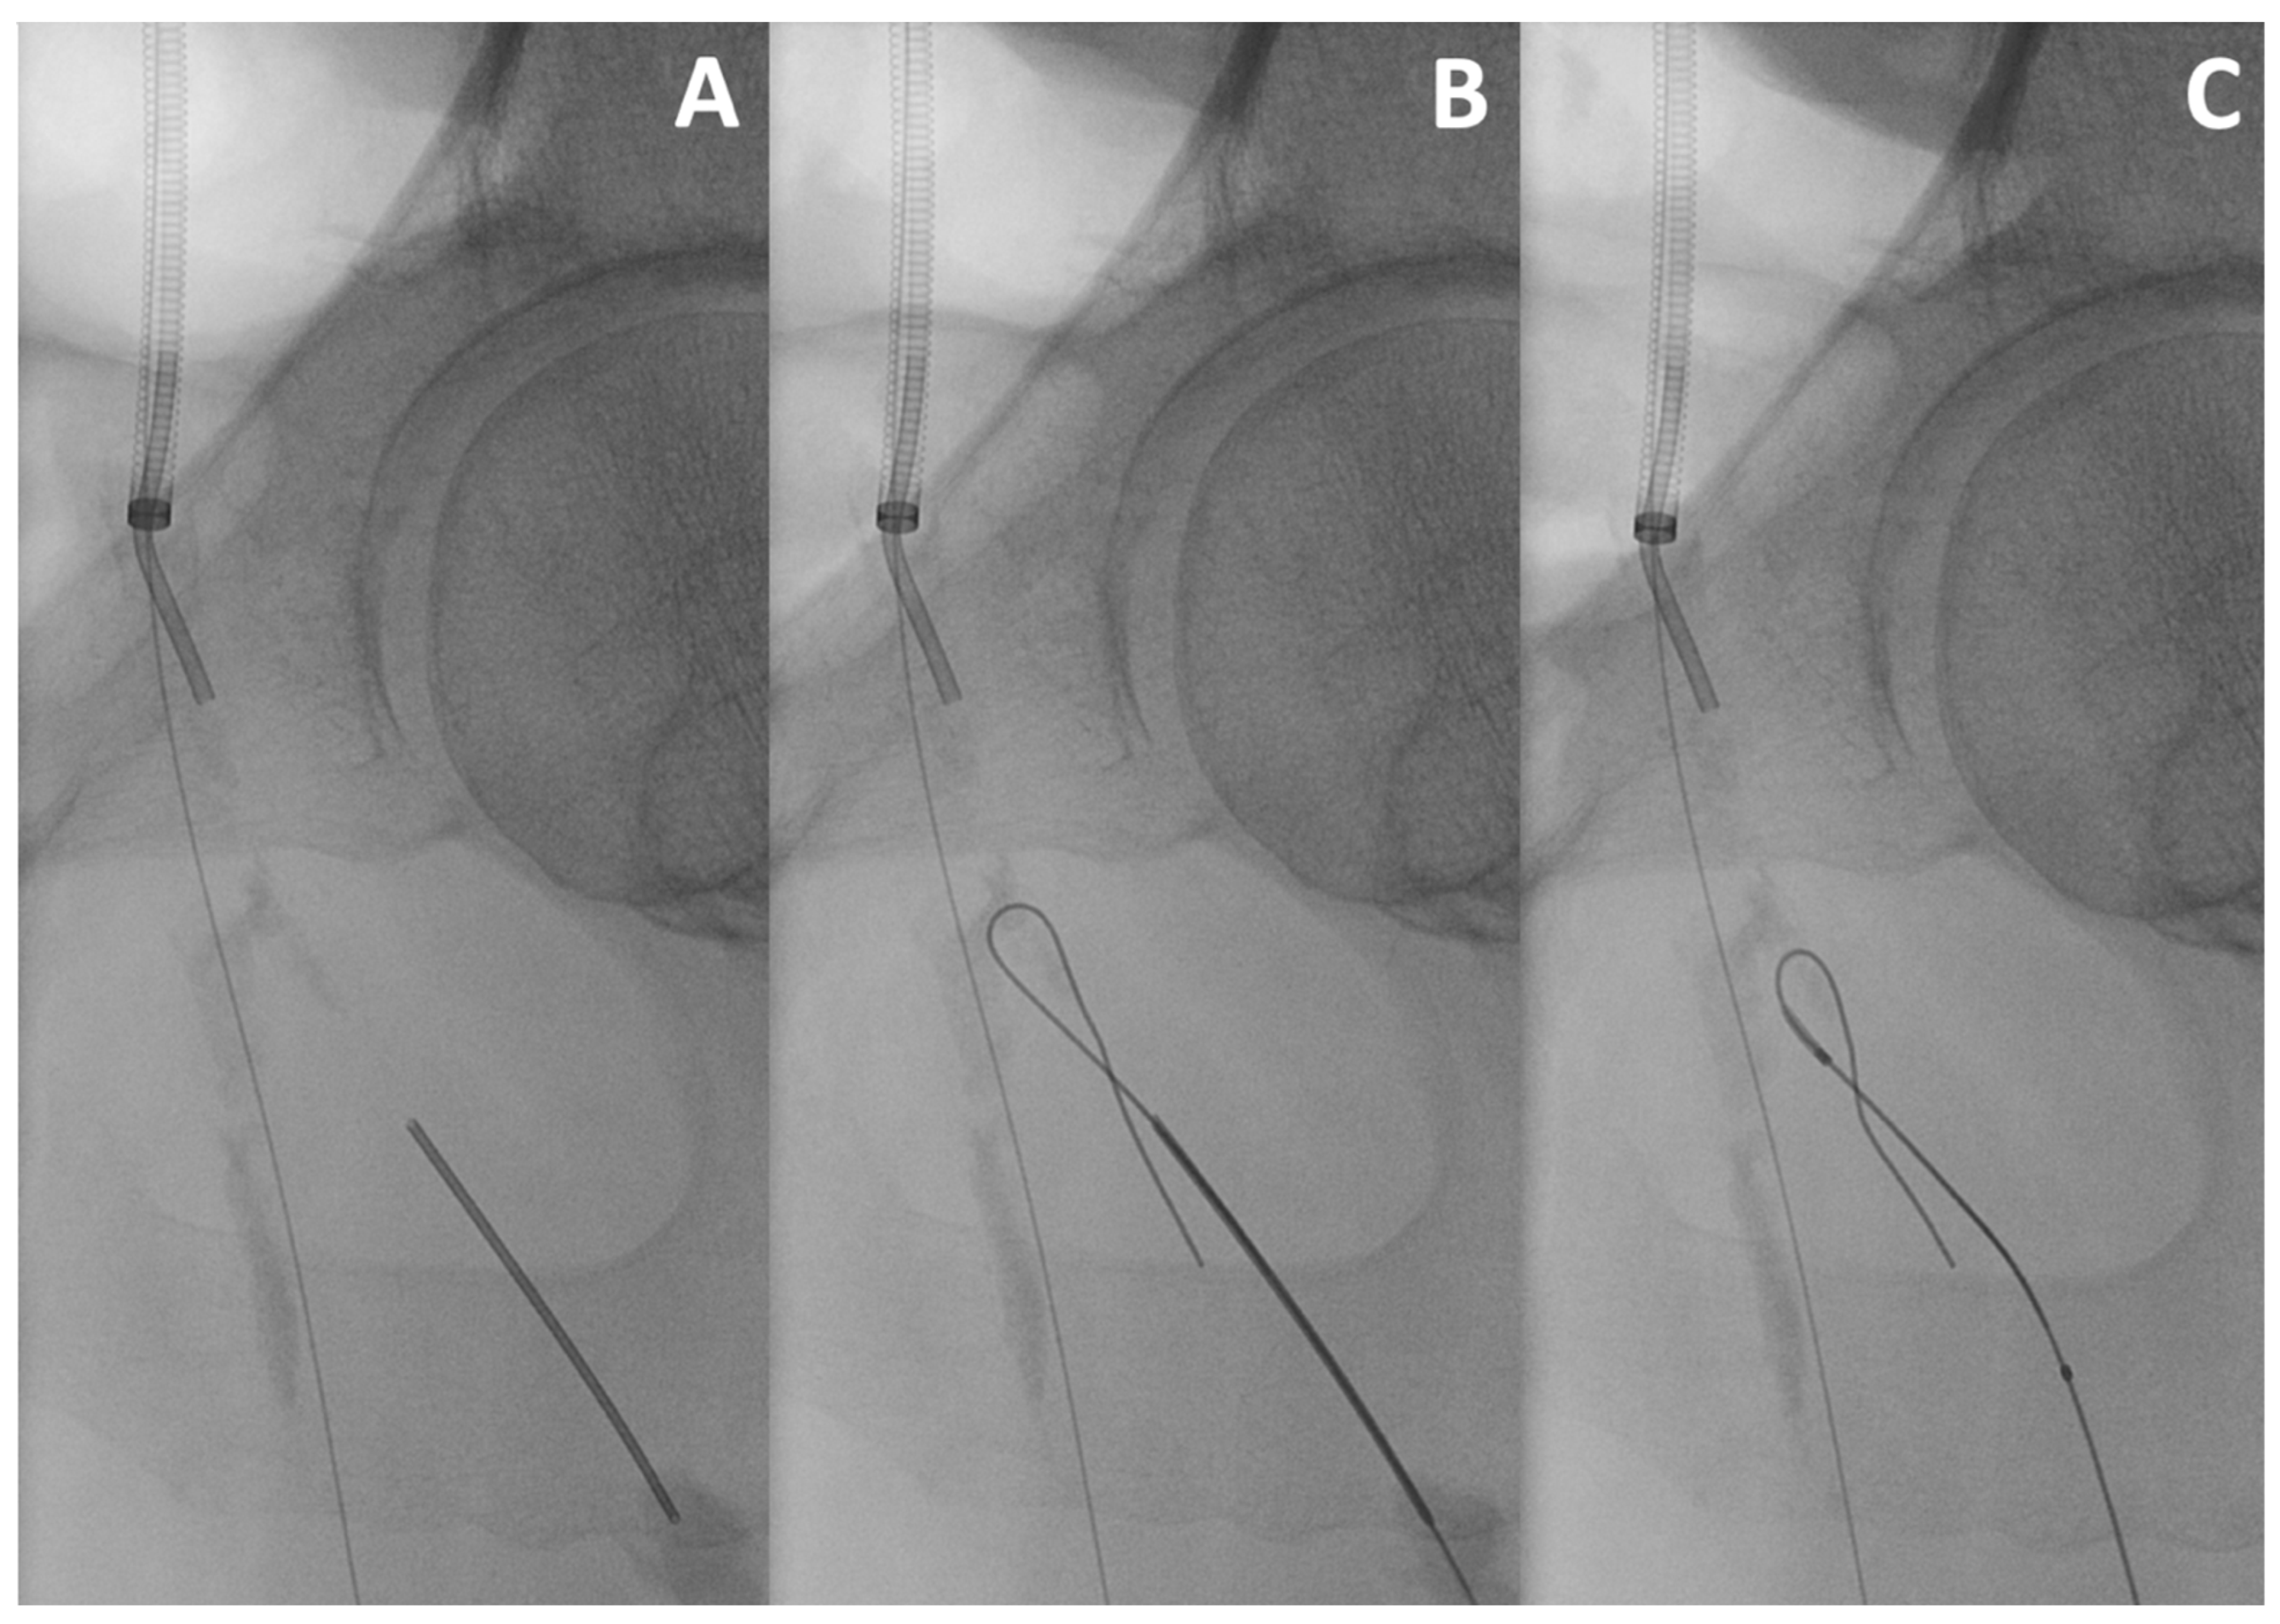

This useful bail-out manoeuvre can be used when the SFA or the DFA cannot be catheterised through an antegrade approach. There is a paucity of data delineating retrograde deep femoral artery access, with first descriptions dating back to 1990 [25,42,43,44]. Retrograde SFA puncture can be easily performed under ultrasound-guidance and is as such not a challenge per se. DFA puncture is more difficult. It is generally performed under fluoroscopic guidance using a 21 or 22 Gauge micropuncture needle after positioning the C-arm in an ipsilateral oblique view. It can also be performed under ultrasound when its course is not too deep. A 0.018″ wire is then inserted over a support catheter to be captured and externalised in the antegrade access and allows for lesion crossing (Figure 2).

Figure 2.

Retrograde deep femoral artery access. After sheath insertion into the common femoral artery via a cross-over approach, retrograde access via puncture of the deep femoral artery with a 21-Gauge micro-puncture needle is performed (A). The 0.018″ guidewire is advanced into the femoral bifurcation (B). A 0.018″ support catheter is placed, and the guidewire is further advanced in a looped manner to cross the lesion without sheath insertion (C).